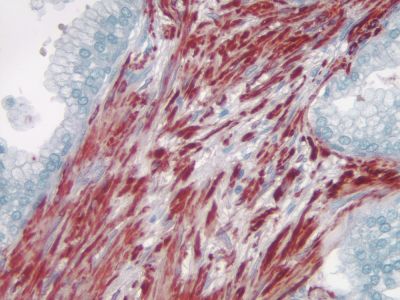

?The ImmPRESS polymerized reporter enzyme staining system uses novel conjugation and micropolymer chemistries to create a highly sensitive, ready-to-use, one-step, non-biotin detection system for immunohistochemistry and immunocytochemistry staining. This unique micropolymer of highly active horseradish?peroxidase (HRP)?is attached to our affinity purified secondary antibodies, producing reagents with outstanding sensitivity and low background.

The peroxidase micropolymers of the ImmPRESS HRP polymer reagent limit steric interference and provide enhanced accessibility to the target, avoiding the disadvantages of other polymer systems that use large dextrans or other macromolecules as backbones. The result is crisp, strong staining of antibody targets, especially nuclear and membrane antigens (such as Ki67, estrogen receptor, bcl-2, CD3, CD8 and CD10) and greater sensitivity than other polymer systems.

The staining procedure is simple as shown in the diagram below. Following a blocking step with the diluted normal horse serum, sections are incubated with primary antibody. After a brief wash, the appropriate ImmPRESS Reagent is added to the sections and incubated for 30 minutes. Sections are again rinsed and the slides are developed with the peroxidase substrate of choice.